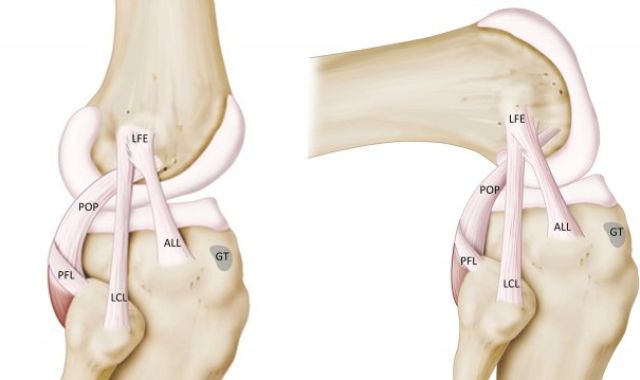

Antero-Lateral Ligament (ALL) Augmentation

The anterolateral ligament(ALL) is a ligament on the lateral aspect of the human...

ACL rupture and associated structural injuries of the knee

The ACL (anterior cruciate ligament) is part of a complicated network of ligaments that help...